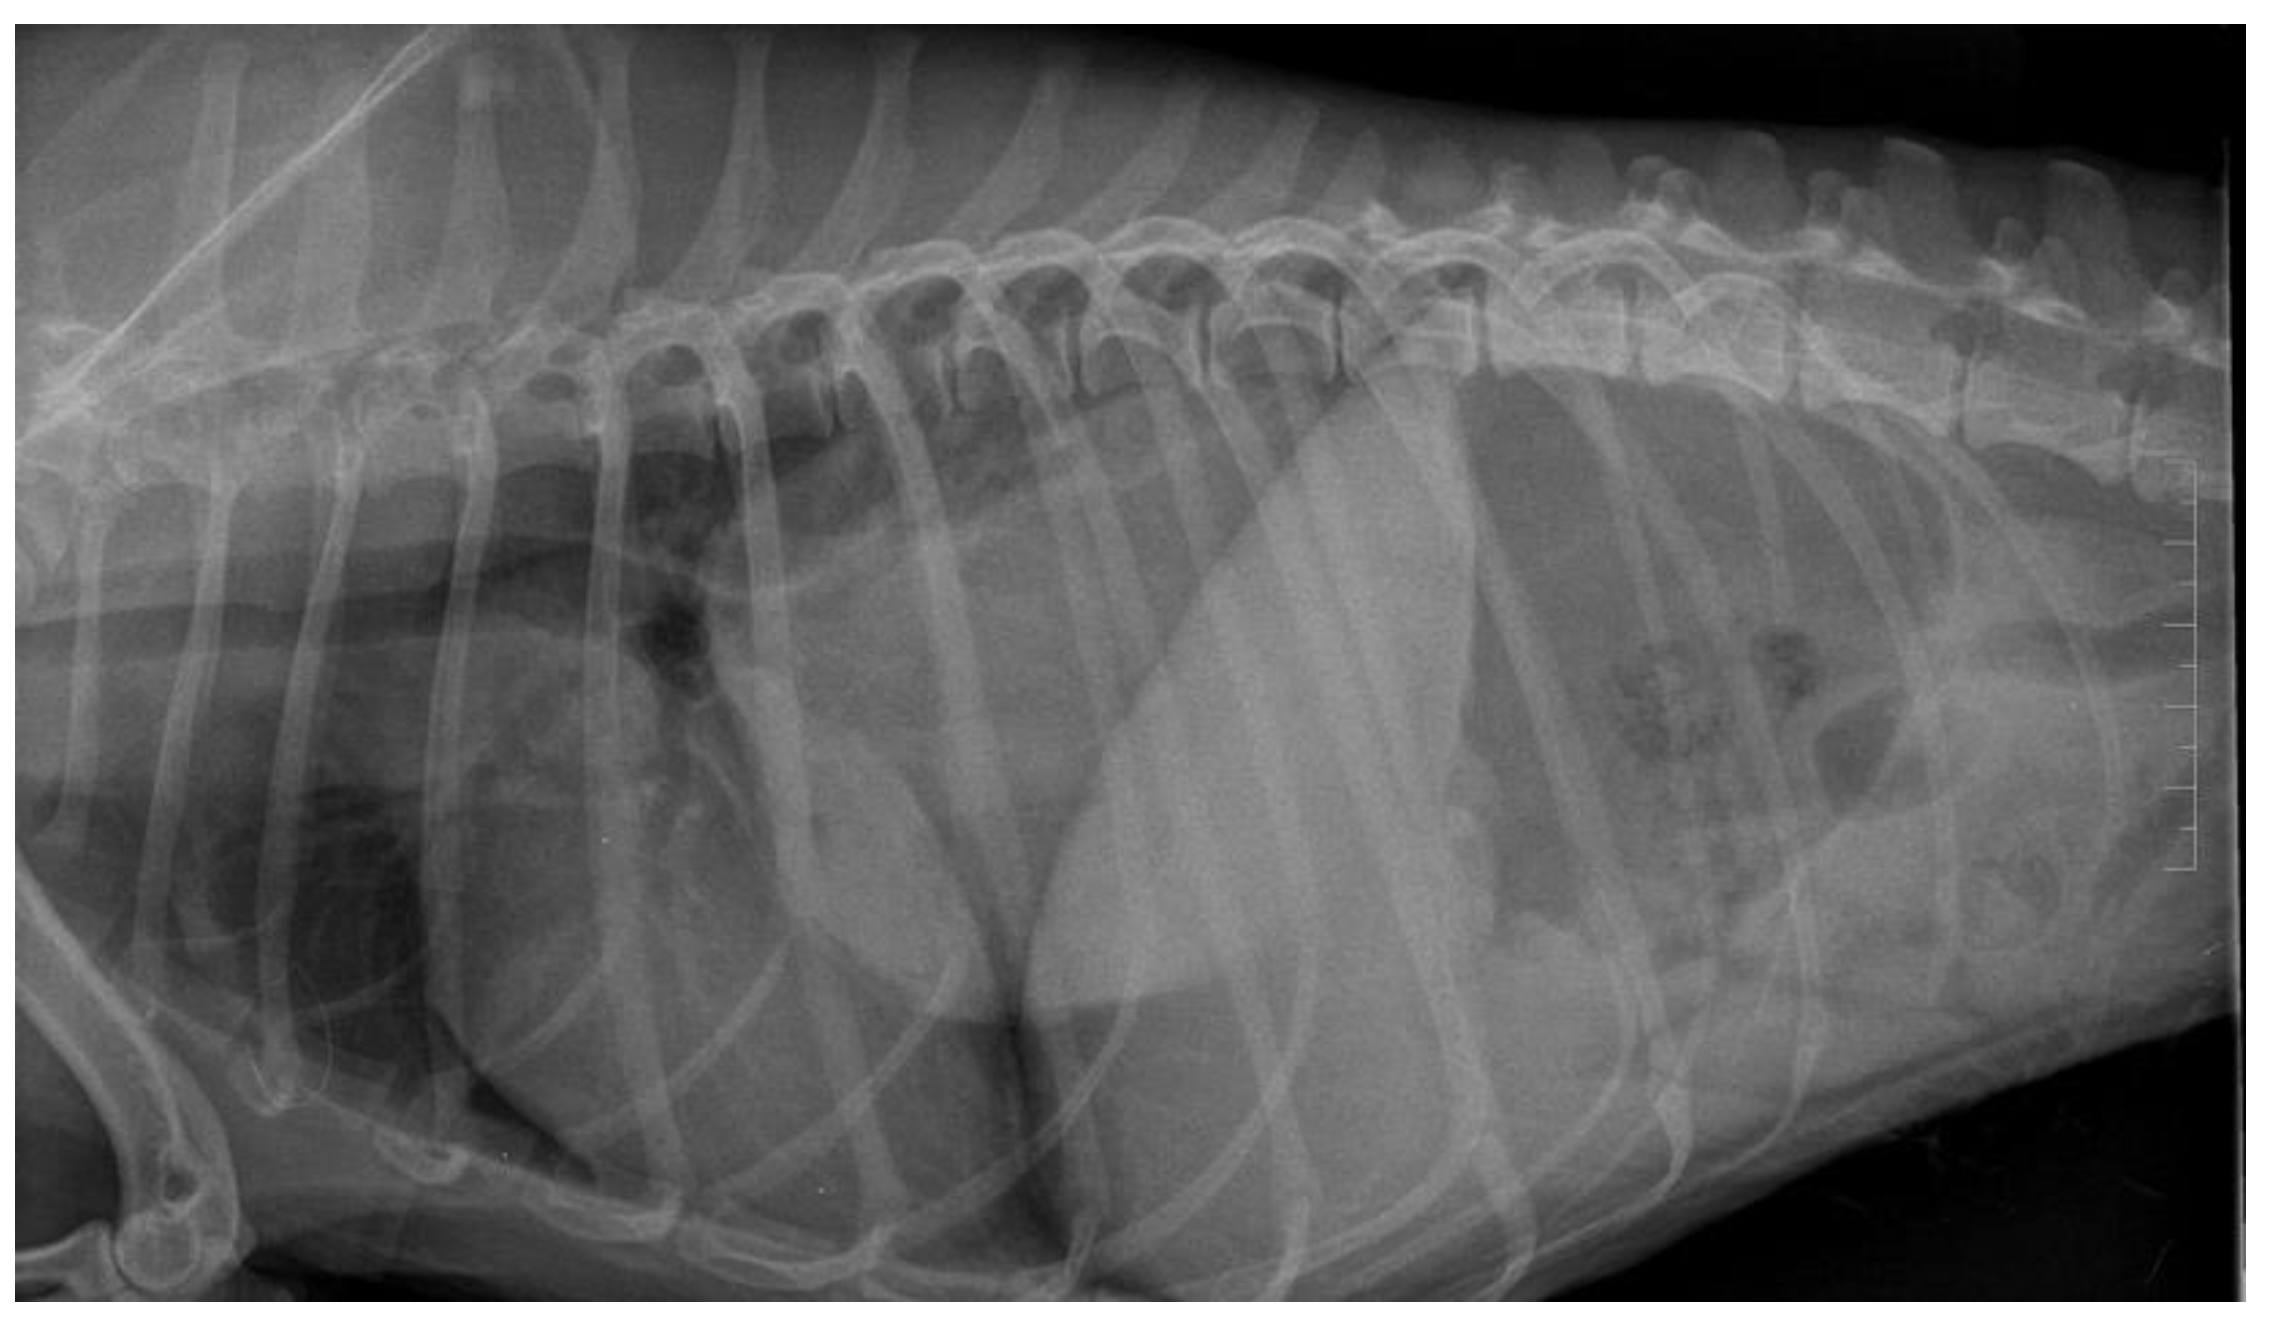

Water In Dog's Lungs From Swimming. fluid in dogs' lungs can cause difficulty breathing, and in severe cases can be fatal. Fortunately, there are many treatment options available for this condition. if water has gotten into your dog’s lungs, it could take hours or in some cases even days for signs to show. An abnormal amount of fluid accumulates in. dogs (like humans) who inhale a small amount of water are at risk of something called dry drowning where the inhaled water irritates the lungs. fluid in the lungs in dogs is also known as pulmonary edema. In this article, we will discuss the causes and treatments for pulmonary edema in dogs. a common cause of water in the lungs is chronic valve disease, but other heart problems can lead to pulmonary. dogs can easily fall into unfenced pools, ponds, bathtubs, or other bodies of water with steep sides and no way out. The most common symptoms include coughing or hacking, signs of chest pain, difficulty breathing or wheezing, and extreme lethargy. dry drowning in dogs, also known as secondary drowning, is a potentially fatal condition that occurs when a dog inhales water into their. If you suspect your dog may be suffering from dry drowning, take your dog to the vet immediately.

fluid in the lungs in dogs is also known as pulmonary edema. An abnormal amount of fluid accumulates in. If you suspect your dog may be suffering from dry drowning, take your dog to the vet immediately. dogs (like humans) who inhale a small amount of water are at risk of something called dry drowning where the inhaled water irritates the lungs. a common cause of water in the lungs is chronic valve disease, but other heart problems can lead to pulmonary. Fortunately, there are many treatment options available for this condition. The most common symptoms include coughing or hacking, signs of chest pain, difficulty breathing or wheezing, and extreme lethargy. if water has gotten into your dog’s lungs, it could take hours or in some cases even days for signs to show. fluid in dogs' lungs can cause difficulty breathing, and in severe cases can be fatal. dogs can easily fall into unfenced pools, ponds, bathtubs, or other bodies of water with steep sides and no way out.